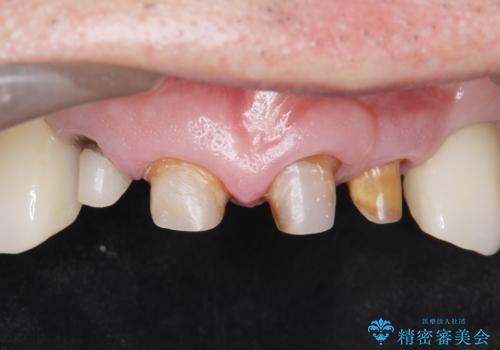

- 前歯の被せ物がとれたまま放置されていた患者様です。

前歯4本のうち3本の被せ物が脱離し、残りの1本の被せ物は劣化し変色していました。

古い被せ物や土台・虫歯をしっかり除去したのち、セラミック治療を行いました。